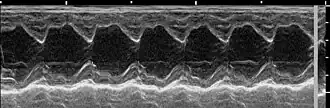

Echokardiografie

Die Echokardiografie ist als Standardverfahren unverzichtbar: Sie erlaubt eine Bestätigung der Diagnose, eine Feststellung des Schweregrades und der wahrscheinlichen Ursache sowie eine Beurteilung des Verlaufs. Infolge der verbesserten Darstellungsqualität der Ultraschallbilder ist eine TEE heute nur noch bei weniger als fünf Prozent der Patienten zwingend erforderlich.[19]

Die Farbdoppler-Echokardiografie (s. Abb.) zeigt eine vorhandene Mitralinsuffizienz als (meist blau dargestellte) Farbwolke im linken Vorhof, die als Insuffizienzjet oder Regurgitationsjet bezeichnet wird. Breite und Ausdehnung dieser Farbwolke erlauben bereits eine grobe Abschätzung des Schweregrades der Insuffizienz. Darüber hinaus können meist bei der Echokardiografie bereits der zugrundeliegende Mechanismus (Ringdilatation, inkompletter Klappenschluss, Endokarditis, Prolaps, flail leaflet, „unklar“) und die Lokalisation eventueller Klappenveränderungen dokumentiert werden.[20]

Auch die Größe und Pumpfunktion des linken Ventrikels können mit Hilfe der Echokardiografie zuverlässig ermittelt werden. Diese wichtigen Kenngrößen der Herzfunktion sind für die Beurteilung einer schweren Mitralinsuffizienz wichtig, da sie Aufschluss über den optimalen Zeitpunkt einer Klappenoperation geben.